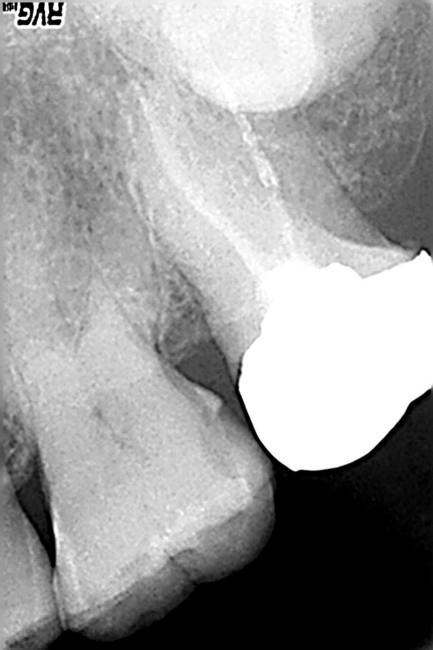

このうち健診などで見落としがちになるのが隣接面う蝕です。隣接面う蝕を初期のうちに見つけるには私たち歯科医でもかなり経験と熟練を要します。歯間離開器という器具を用いて隣り合う歯を少し開いてみないとなかなか分りません。下の写真は数ヶ月前には見つけられなかった隣接面う蝕のレントゲン像と口腔内写真です

写真で左の歯(上顎第一大臼歯)が右の金属冠に接するところで隣接面う蝕になっています。